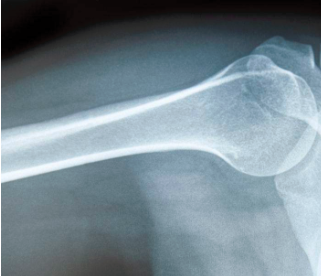

妈妈听完,笑了笑,耐心地解释道:“今天,妈妈就来给讲讲影像学的知识,然后你就知道X光、CT、MRI、B超的区别了。你说的‘拍片’,就是指X光检查。X光有很强的穿透能力,检查时就像给身体内部拍了一张平面影像的照片。当然,由于被照射的物体密度不均匀,拍摄之后,就会在底片上形成黑白不一的颜色。”

明明追问道:“骨头是不是白色的呢?”妈妈回答道:“对,所以骨折或者骨质增生的辅助检查,首选X光。”